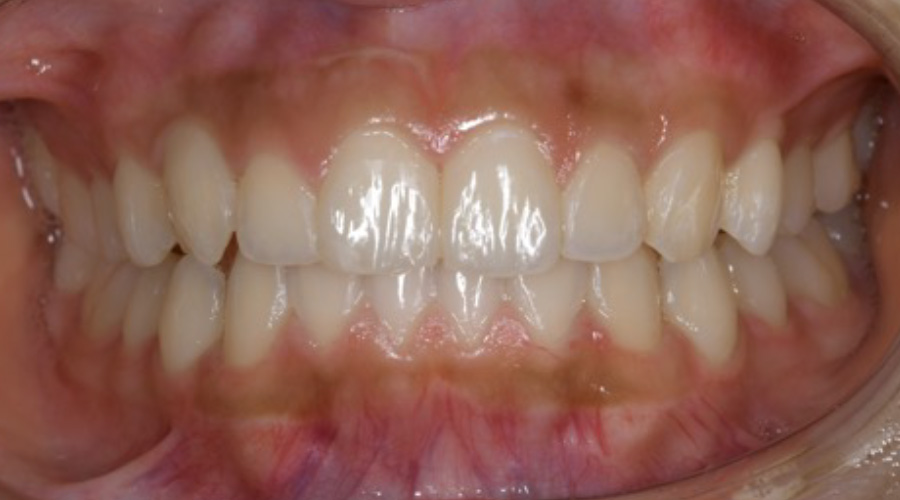

歯を矯正したい

【マウスピース矯正】

- 主訴

- 矯正希望

- 期間

- 5年

- 費用

- マウスピース矯正とプレミアムホワイトニングセット

1,280,340円(税込)

- 治療内容

- 目立ちにくいマウスピース矯正(非抜歯矯正)

歯と歯の間に隙間をつくることにより、歯列弓を広げながら治療を行いました。

また矯正用マウスピースをトレー代わりにし、ジェルを入れてホームホワイトニングを同時に行っております。

- 治療に伴うリスク

- ・後戻りする可能性があるのでリテーナーを最低でも矯正期間以上はつけること

・ホワイトニング後、一時的に痛みが出る場合があります

・稀にほっぺた、唇、舌などに口内炎や傷ができることがあります